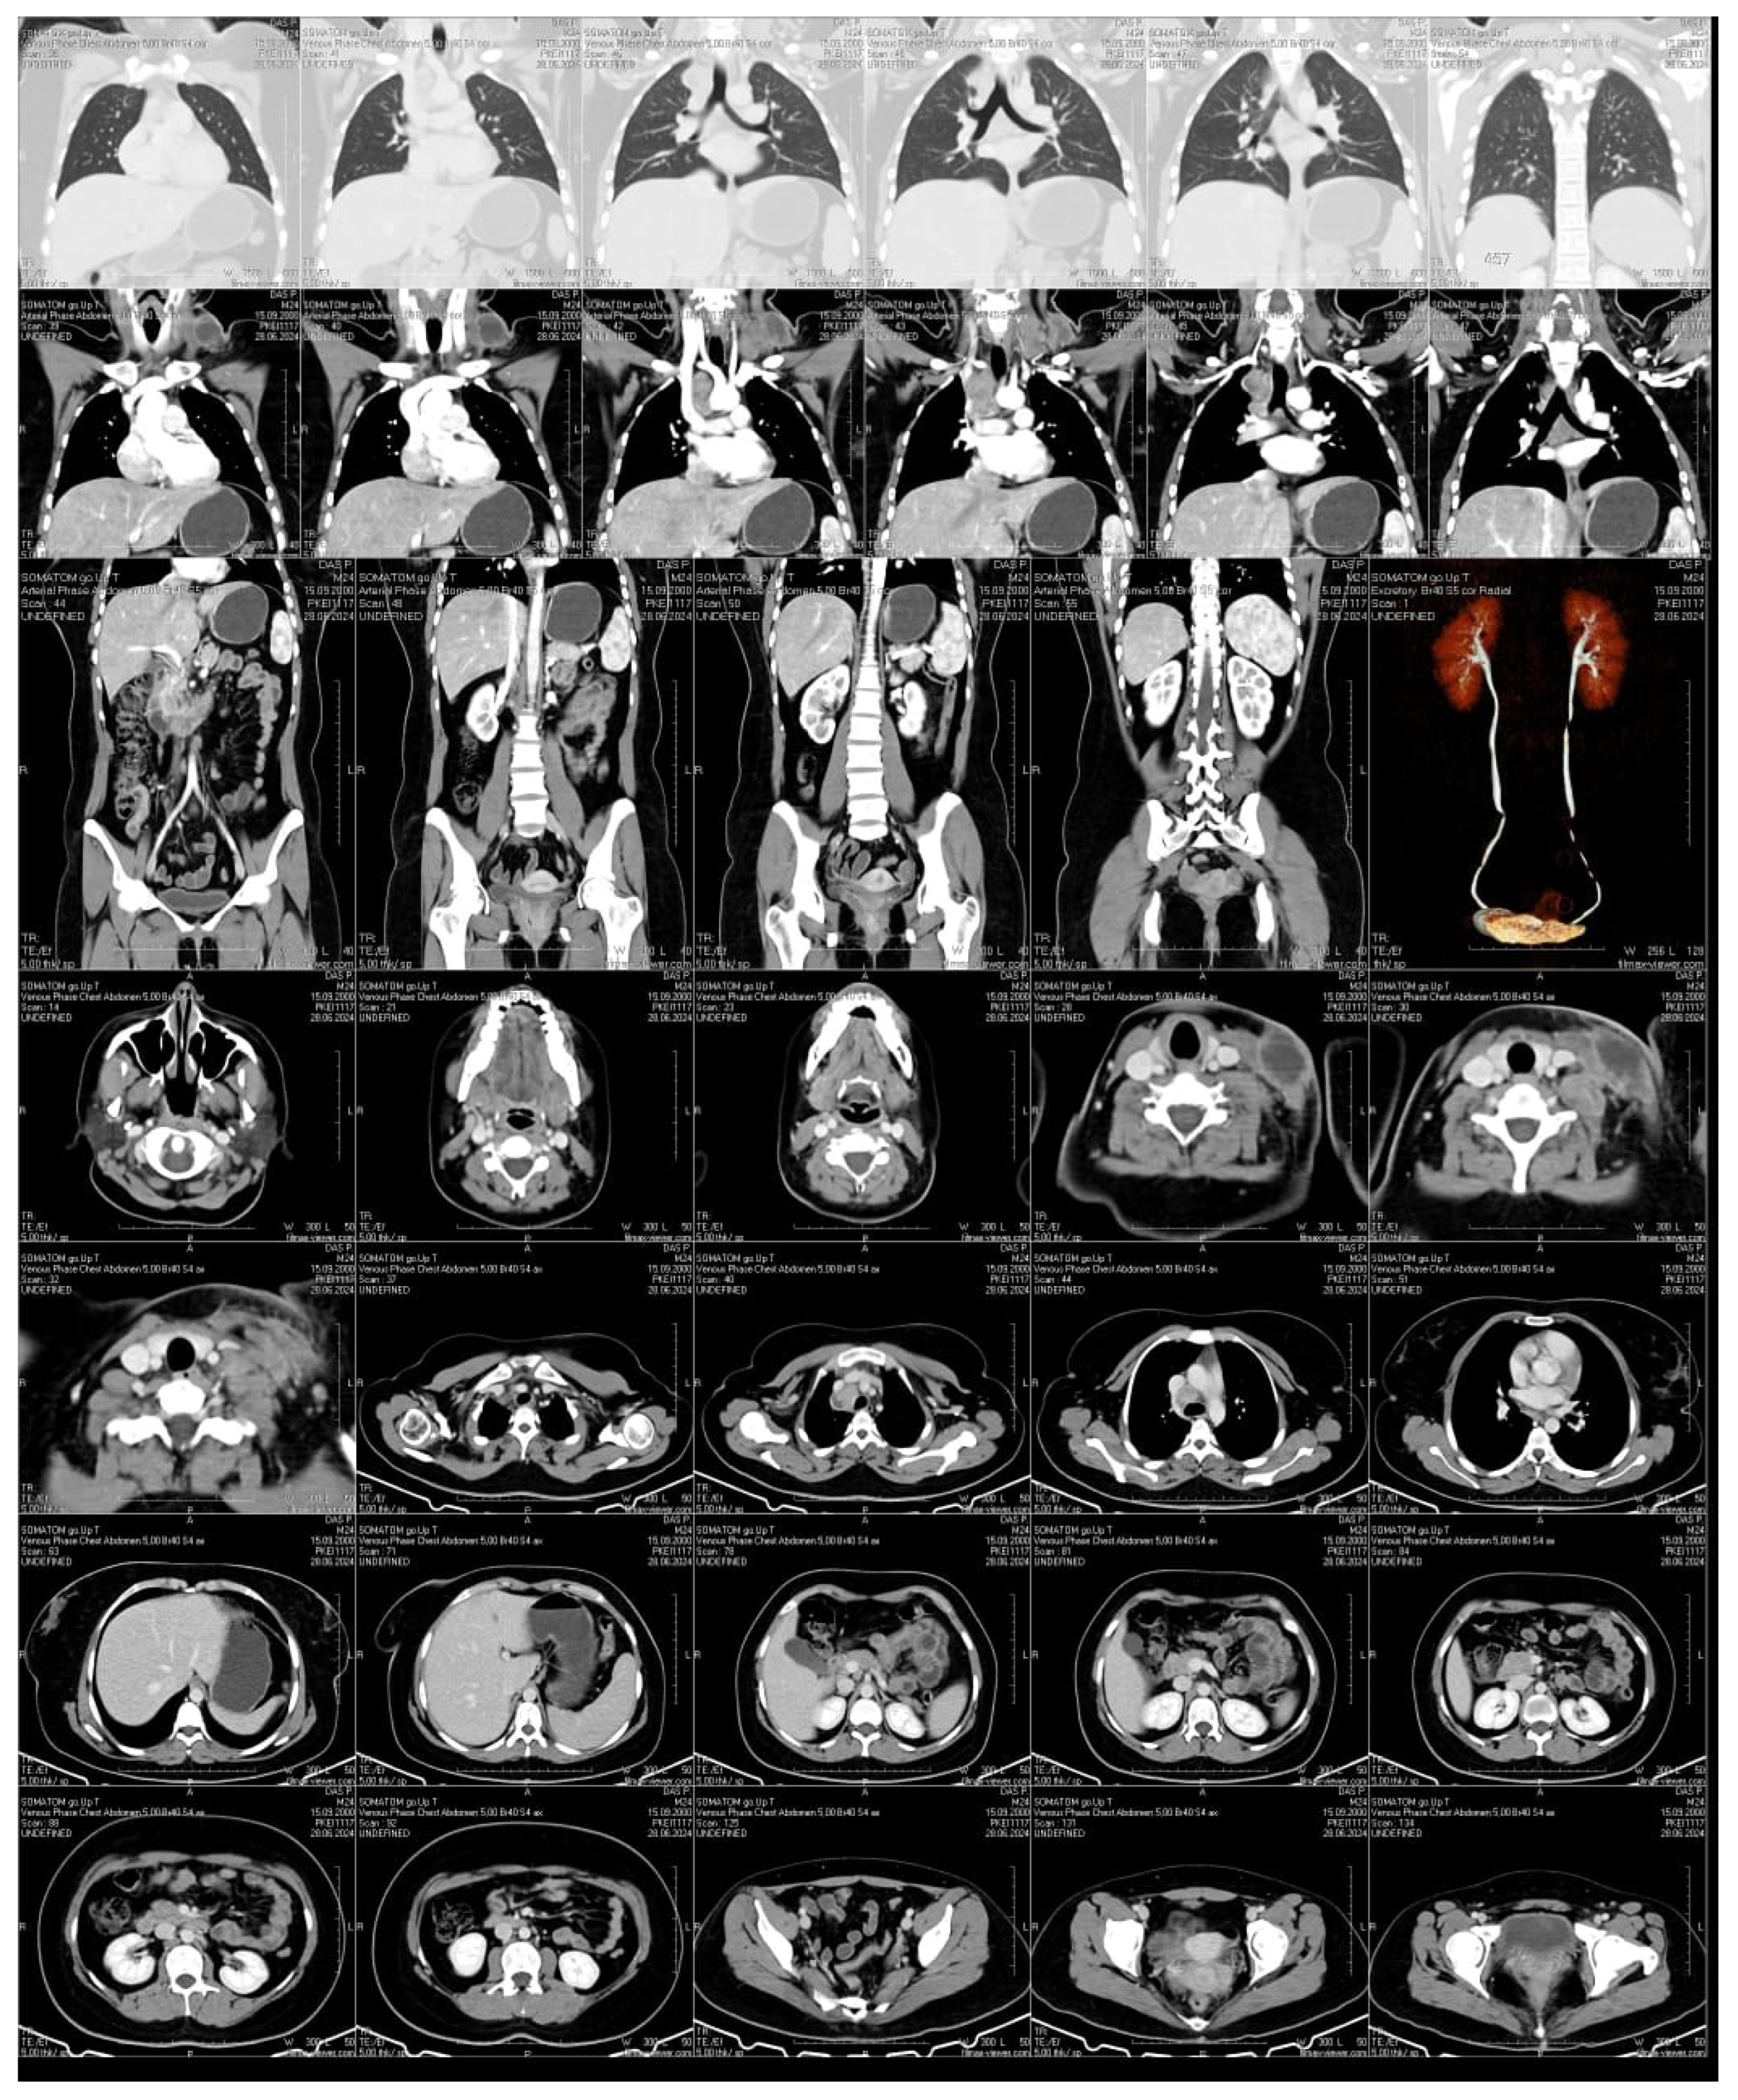

We describe the case of a 24-year-old woman who developed a swelling under her collarbone, along with fever, swollen lymph nodes, tiredness, and weight loss. These symptoms started about three months after she had a moderate COVID-19 infection. Blood tests showed a high white blood cell count, with more neutrophils and fewer lymphocytes, as well as high levels of inflammation markers. Serological and molecular diagnostics confirmed Epstein-Barr virus (EBV) reactivation.. Despite receiving antiviral and supportive treatment, her condition worsened. Advanced imaging showed that her lymph nodes remained swollen and started to break down. Doctors ruled out other possible causes, such as bacterial infections, blood cancers, autoimmune diseases, and cancer spread. A needle biopsy, combined with a special genetic test (PCR), confirmed the presence of Mycobacterium tuberculosis, the bacteria that cause tuberculosis. She started a standard tuberculosis treatment, which led to major improvement within two months. Her swollen lymph nodes shrank, and her inflammation markers returned to normal. This case shows how COVID-19-related immune system changes, EBV reactivation, and tuberculosis infection can be connected. It highlights the need for careful monitoring of patients with long-lasting swollen lymph nodes, especially those with weakened immune systems.